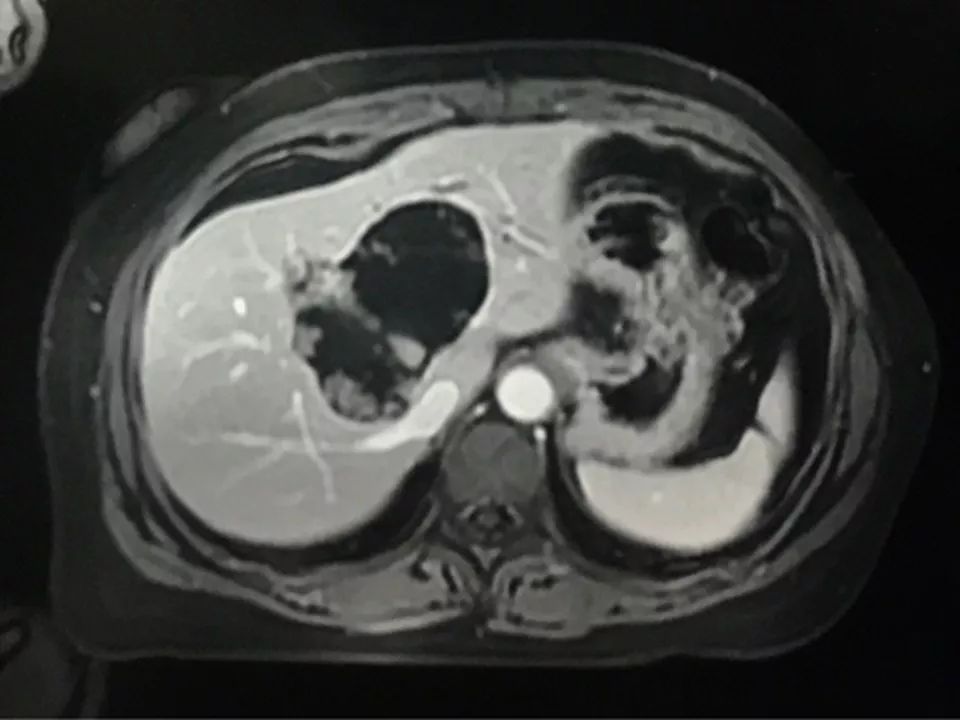

MRI表现:

肝内单发占位灶,累及肝左右叶及尾叶。T1WI示病灶以低信号为主,边缘多枚等信号结节,正反相位未见明显脂肪成份;T2WI示病灶以粘液成份为主呈高信号,边缘多枚稍高信号结节(相对肝实质),DWI呈不均匀等高信号,ADC图以高信号为主。动脉期病灶边缘均匀强化,壁结节显著强化,门脉期边缘仍持续强化,边缘光滑,壁结节呈相对等低信号。MRCP示胆管扩张,病灶与胆管相通。